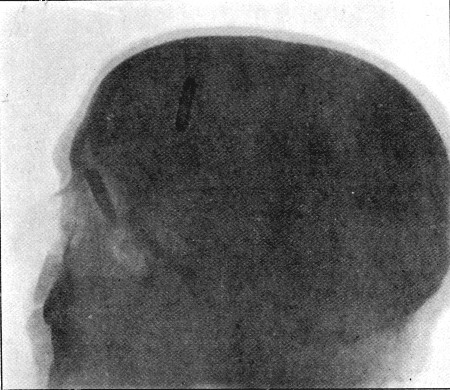

60. Skiagram of Bullet in Nasal Fossa 244

61. Diagram of Aperture of Entry into Cranium 245

62. Aperture of Entry into Frontal Bone 252

63. Fragment of Inner Table Displaced from Opening seen in Fig. 62 253